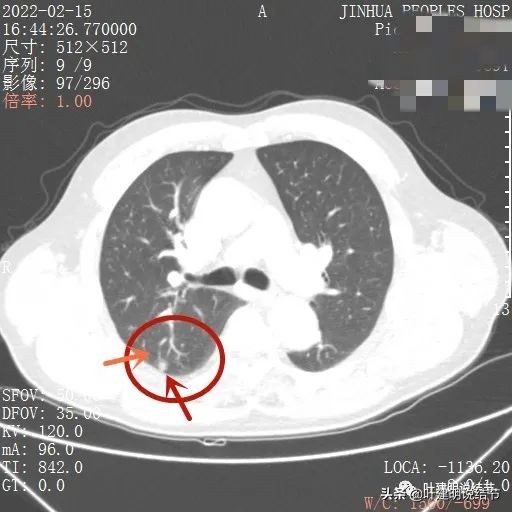

我们再来看薄层的CT图像:

病灶出现,虽然此层面还很小,但也是实性的,有微血管进入(桔色箭头)

上图更清楚显示血管进入病灶,病灶与胸膜间点状相接,感觉病灶有膨胀性,圆形或类圆形的